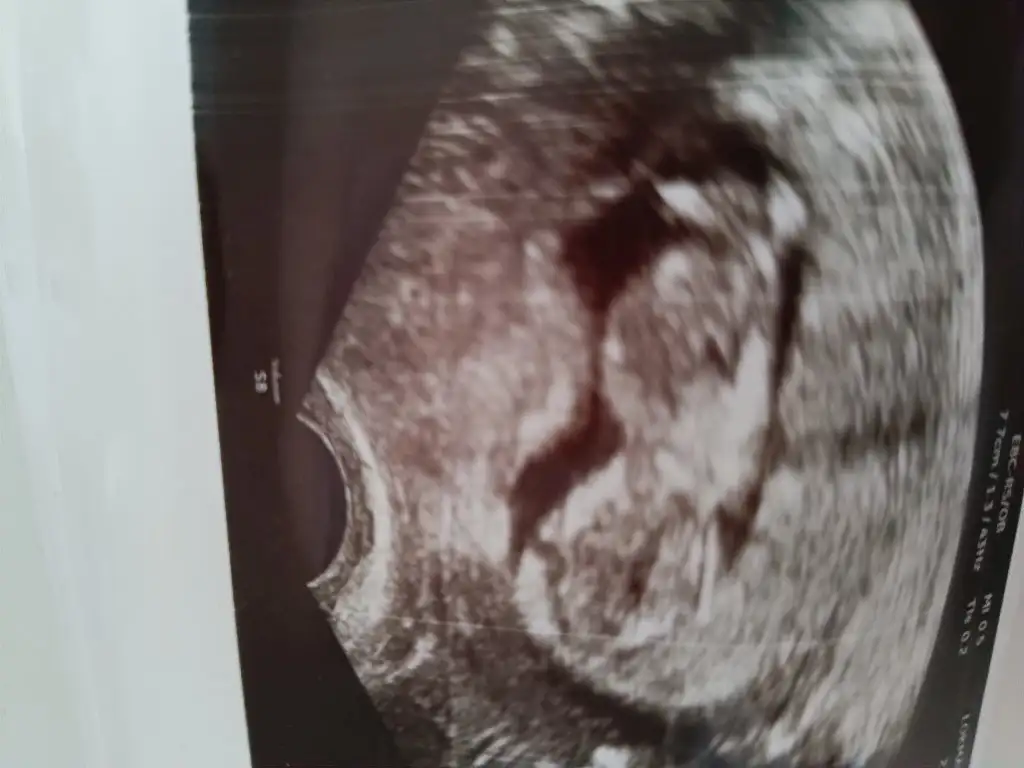

Cinsiyet tahmini yapabilir misiniz

Eklentiler

• IMG_20250224_164751.webp

IMG_20250224_164751.webp

22,5 KB · Görüntüleme: 44